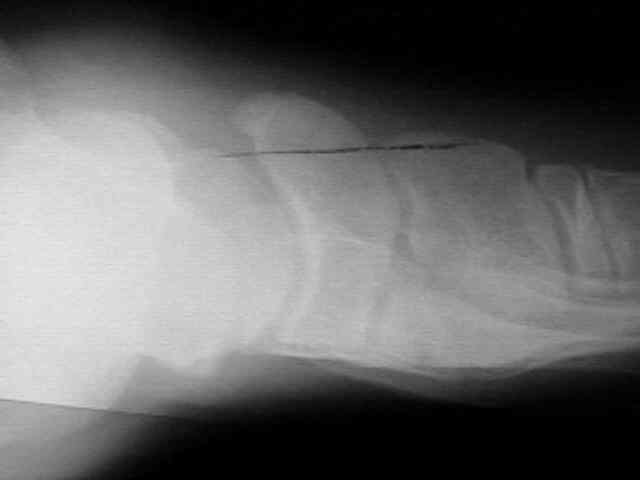

Radiographs

• radiographs may not be helpful if the accessory ossification is not ossified;

• the standard oblique of the foot (medial internal oblique view) will not show the accessory ossicle in profile;

• the lateral (external) oblique view is the radiograph of choice;

• although accessory navicular appears distinct from the navicular on x-rays, it is actually attached by fibrous tissue or cartilage;

Accessory Navicular 2 Accessory Navicular 3 Accessory Navicular 4